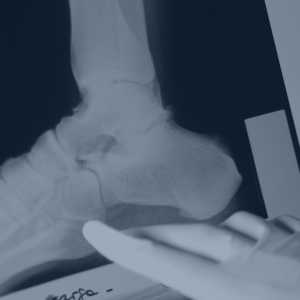

Cirugía mínimamente invasiva: Revolucionando el tratamiento del dolor musculoesquelético